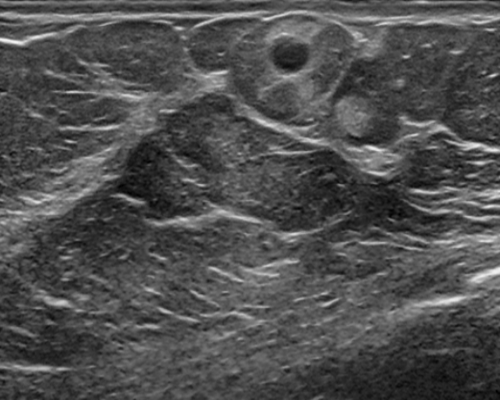

For segmentation, we employ the zero-shot method MedCLIP-SAMv2 [koleilat2024medclip, koleilat2024medclipsamv2]. It works by computing activation maps from a pre-trained CLIP model, and using them as query for the Segment Anything Model (SAM) [kirillov2023segment]. Activation maps are computed using Multi-Modal Information Bottleneck Attribution (M2IB) [wang2023visual], using a target image and a query prompt. Here, we aim at improving the quality of the activation maps on different concepts by leveraging KT. This, in turn, should result in a higher accuracy of the final segmentation. We target four different segmentation tasks: lung nodules segmentation on CT images (UnitoChest), pneumothorax segmentation on CXR images (SIIM Pneumothorax), breast nodule segmentation on ultrasound images (UDIAT), and glioma segmentation in MRIs (BraTS23).

The overall results across all segmentation tasks are presented in Tab. 7. The captions used for inversion are reported in the supplementary material. To compute the M2IB activation maps on the fine-tuned models, we employ descriptive prompts as suggested in [koleilat2024medclipsamv2]. The prompts are reported in Tab. 7 as P1 to P4 for each task. We also report reference results of MedCLIP-SAMv2 on each task. Compared to the original setting of MedCLIP-SAMv2, lung nodules and lung pneumothorax are completely novel concepts. There is also a slight difference in the brain glioma class compared to the original brain tumor task, explained in the supplementary file. We employ three metrics to assess the segmentation quality, namely the Dice-Sørensen Coefficient (DSC), Normalized Surface Distance (NSD), and Intersection over Union (IoU). We report results with different values of fine-tuning learning rate. We can observe an increase in segmentation metrics across all tasks, notably in breast ultrasound (NSD 59.44% to 61.56%) and brain MRIs (NSD 20.97% to 22.26%). For lung nodules and pneumothorax, the improvement is less pronounced, probably because the novelty of the task makes improving more difficult in the MedCLIP-SAM setting. We report some visual examples on breast tumor segmentation in Fig. 5, showcasing the improvements of KT.

Results of knowledge transfer on MedCLIP-SAMv2 with different values of learning rate are shown in Tab. 14. We report illustrative examples of the improvements achieved by knowledge transfer in Fig. 11 and Fig. 12. The captions used for inversion for segmentation can be found in Tab. LABEL:tab:captions-segmentation.